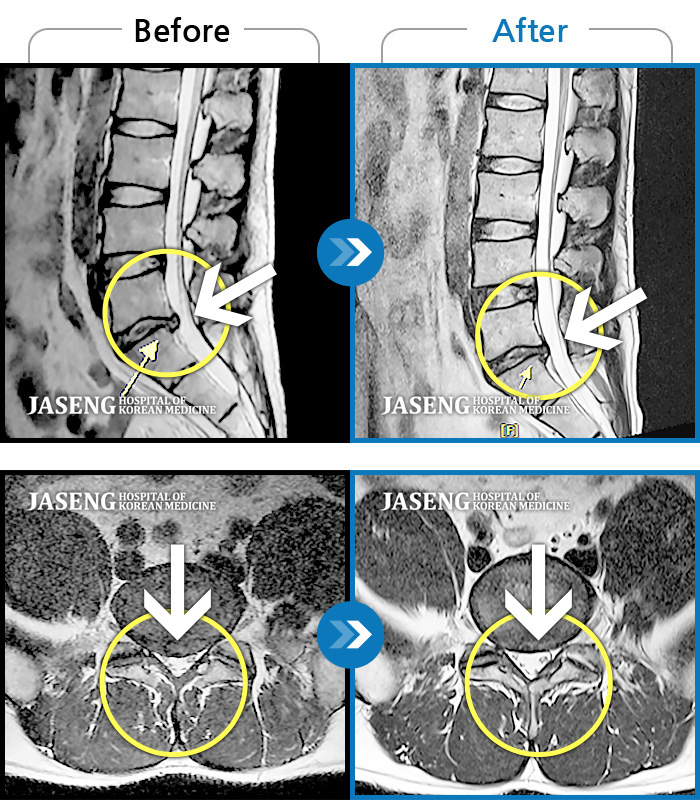

허리디스크

도움받은 사례

광주 · 장영우 원장

좌측 허리 통증으로 허리를 반듯이 펴고 서있기 힘들어 내원하셨습니다.

촬영시기

2024.08.12 ~ 2025.02.26

2025.03.07

조회수 450